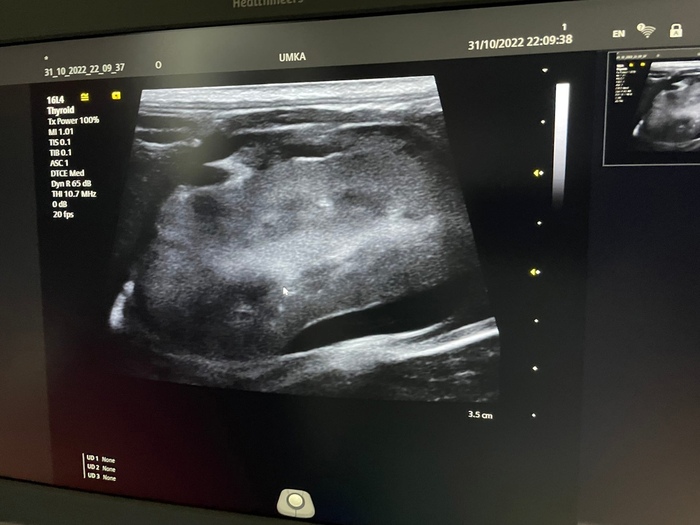

*УЗИ/рентген. С целью оценить состояние внутренних органов (особенно печень, селезенку, почки), лимфоузлы (чаще всего увеличены), наличие или отсутствие свободной жидкости (выпота) в брюшной или грудной полостей при выпотной форме. При ФИП часто наблюдаются увеличение селезенки, изменение структуры печени, изменения в почках. На рентгене можно оценить состояние грудной полости при том же выпоте, т.к. часто при этой форме у кошки затруднено дыхание и часто в клинике начинают именно с рентгенологического исследования.

Вот так выглядит пример выпота (свободная жидкость) в брюшной полости: